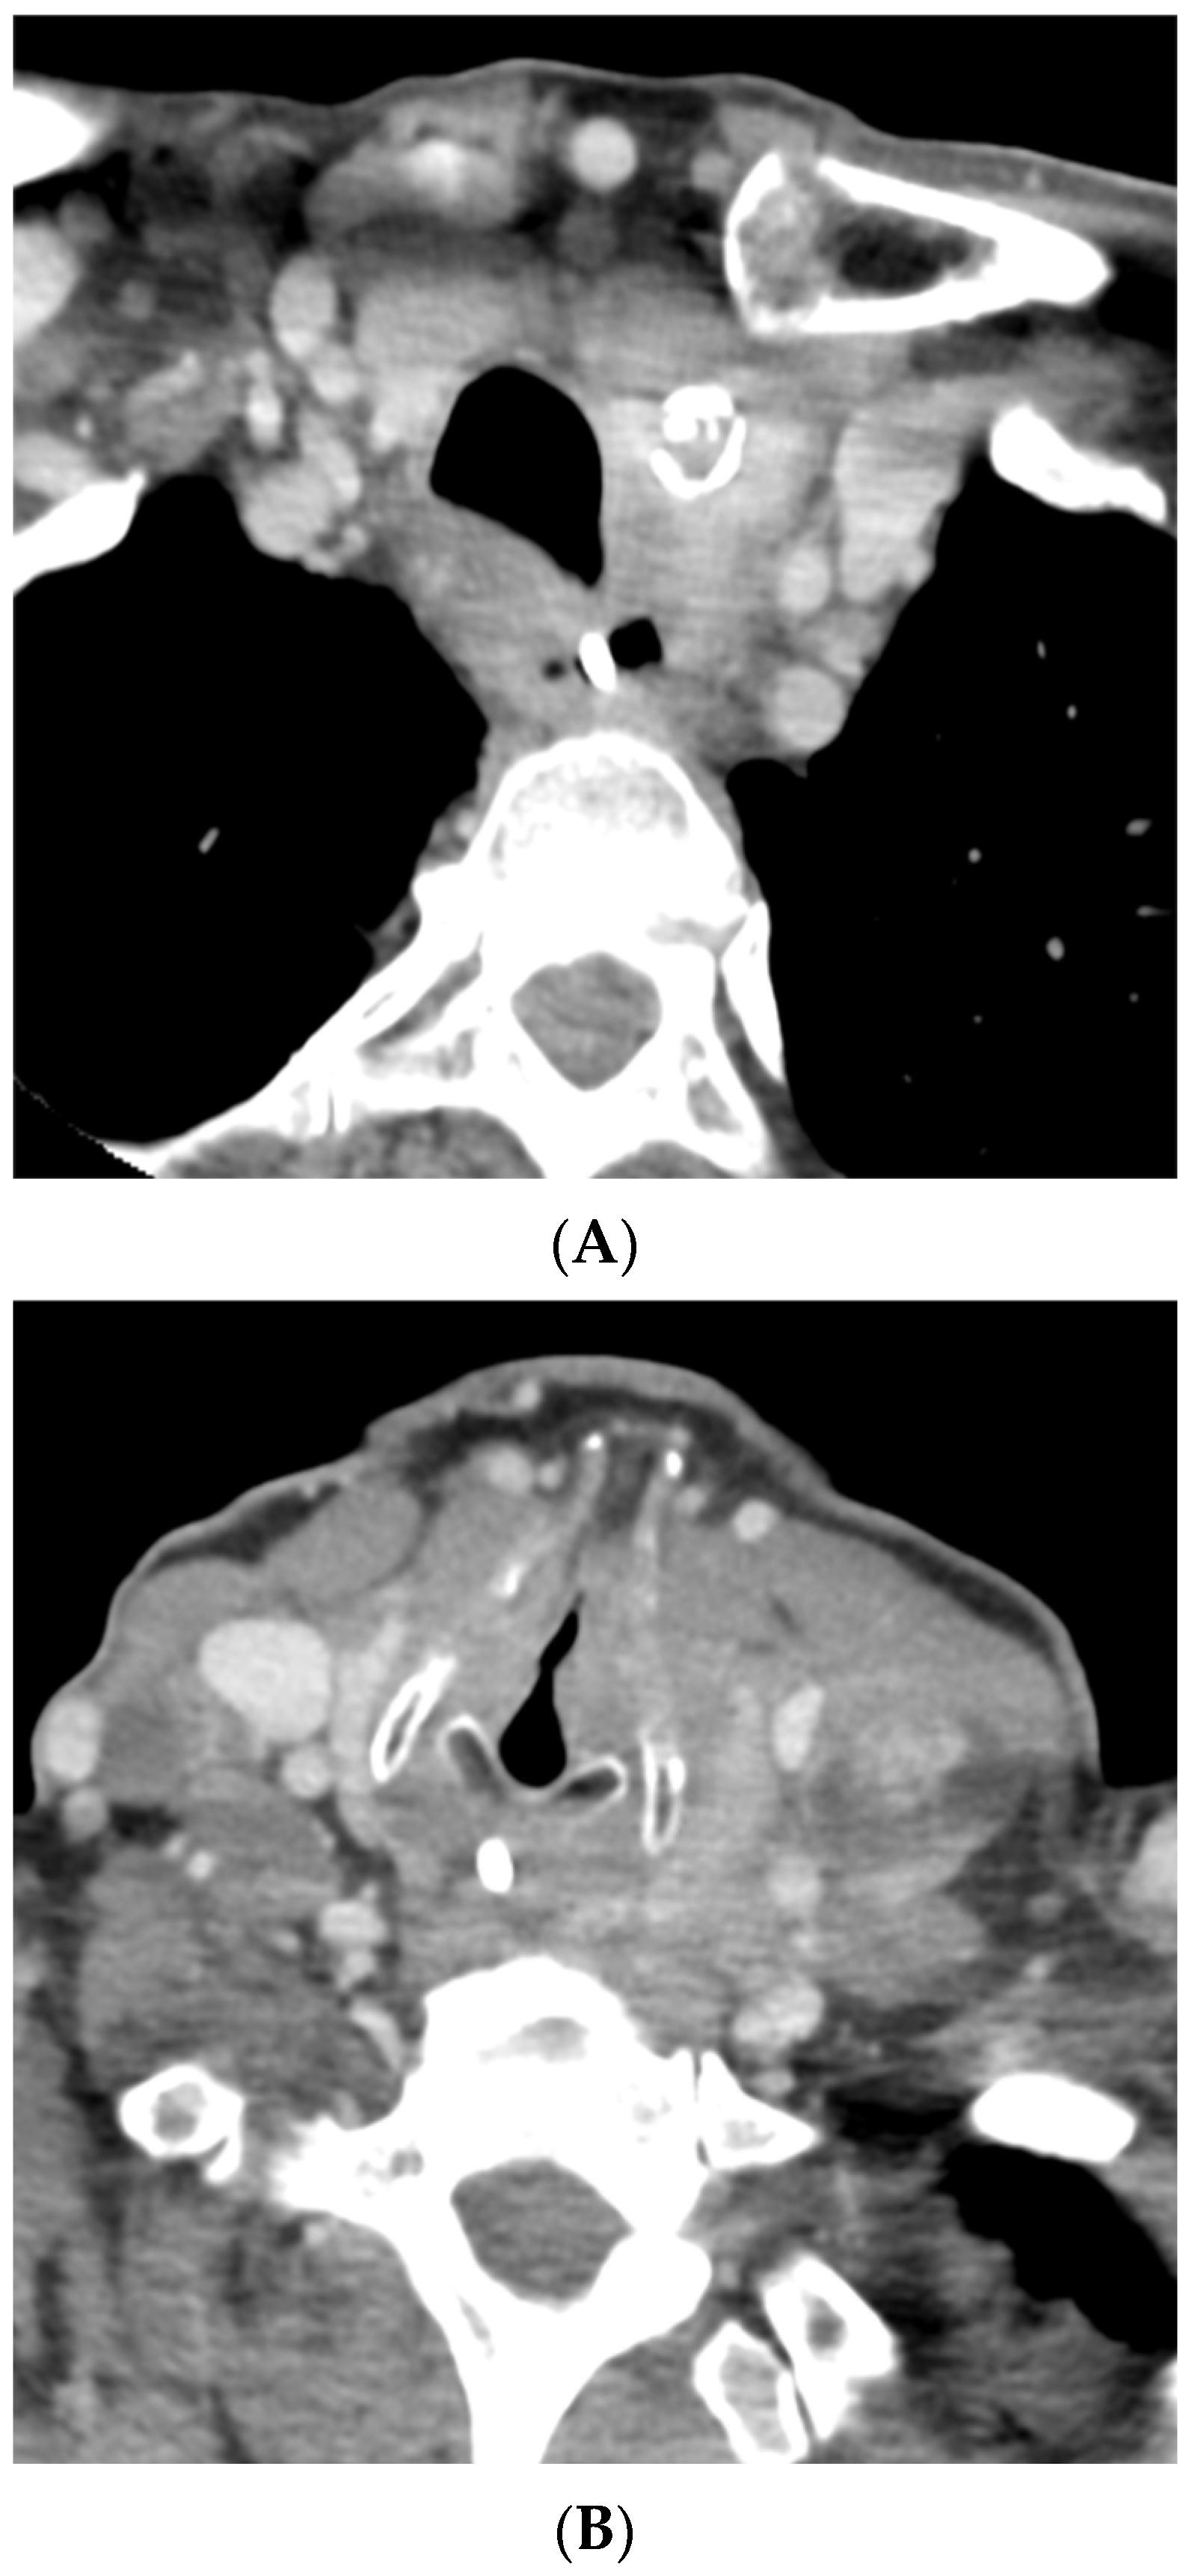

Figure 2.

A follow-up CT of the neck and thorax performed 12 days later demonstrated a significant decrease in the hypo-enhancing (likely anaplastic) component of the mass with residual enhancing mass and adenopathy (likely papillary component) (A,B). (A) Axial image at the level of the second thoracic vertebra. (B) Axial image at the level of the sixth cervical vertebra.